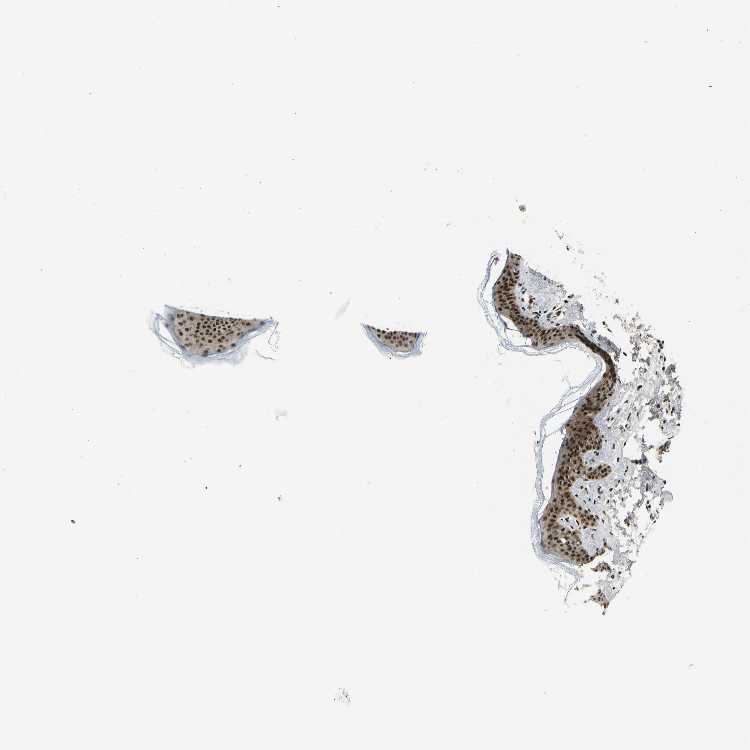

SKIN 1 - Antibody stainingi

Antibody staining in the annotated cell types in the current human tissue is reported as not detected, low, medium, or high, based on conventional immunohistochemistry profiling in selected tissues. This score is based on the combination of the staining intensity and fraction of stained cells.

Each image is clickable and will lead to virtual microscopy that enables deeper exploration of all samples and also displays staining intensity scores, fraction scores and subcellular localization as well as patient and tissue information for each sample.

Antibody HPA017998Antibody HPA018864

Langerhans HighHigh

Fibroblasts HighHigh

Keratinocytes HighHigh

Melanocytes HighHigh

SKIN 2 - Antibody stainingi

Epidermal cells HighHigh